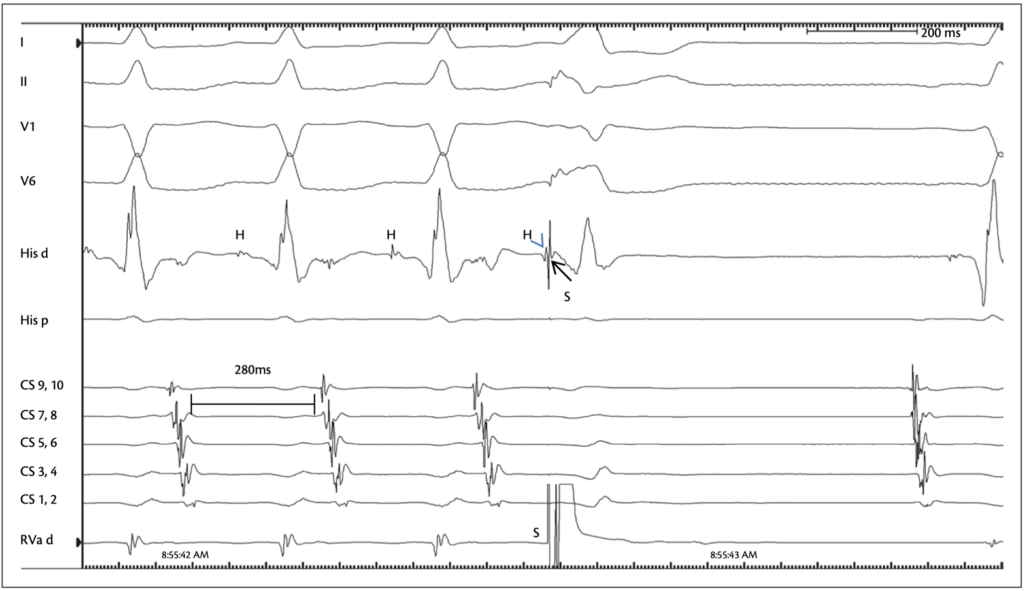

We observe that the patient presents with a tachycardia with 1:1 conduction, with the earliest activation recorded at CS9–10.

A His-refractory extrastimulus is delivered and results in termination of the tachycardia. What is the most likely mechanism?

The only tachycardia that can be terminated by a PVC delivered during the His refractory period is AVRT, as it is His-dependent.